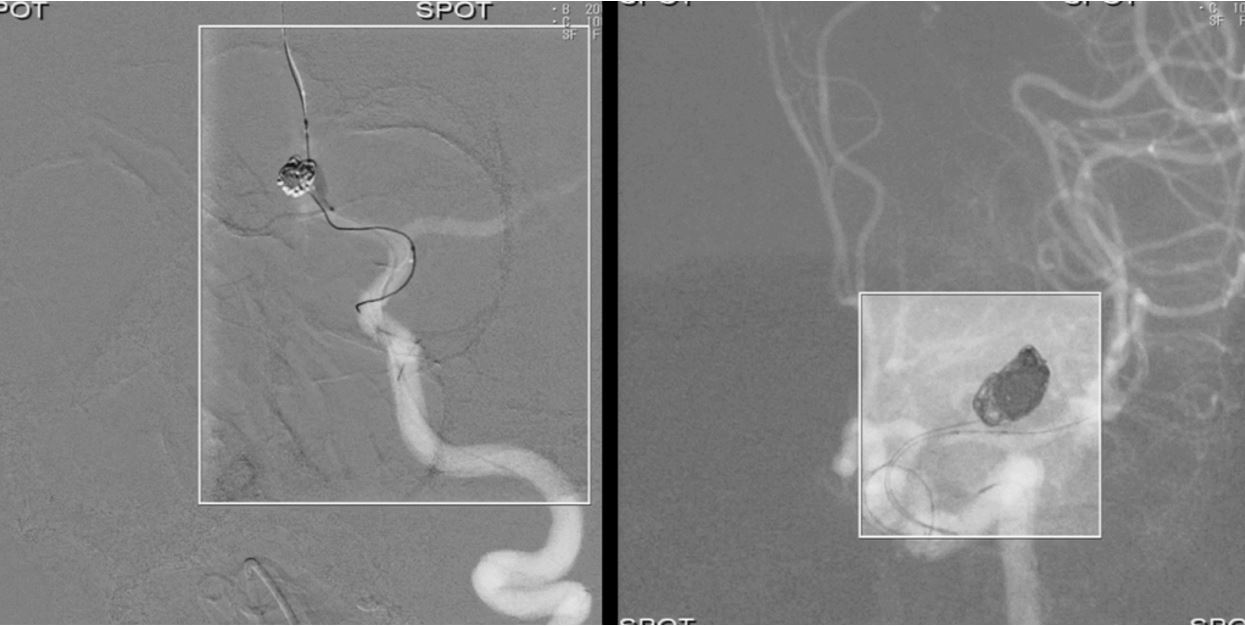

· Режим Spot Fluoro передбачає асиметричну, сфокусовану на проблемній ділянці колімацію з одночасним відображенням оточуючої області та збереженням дози до 70%.